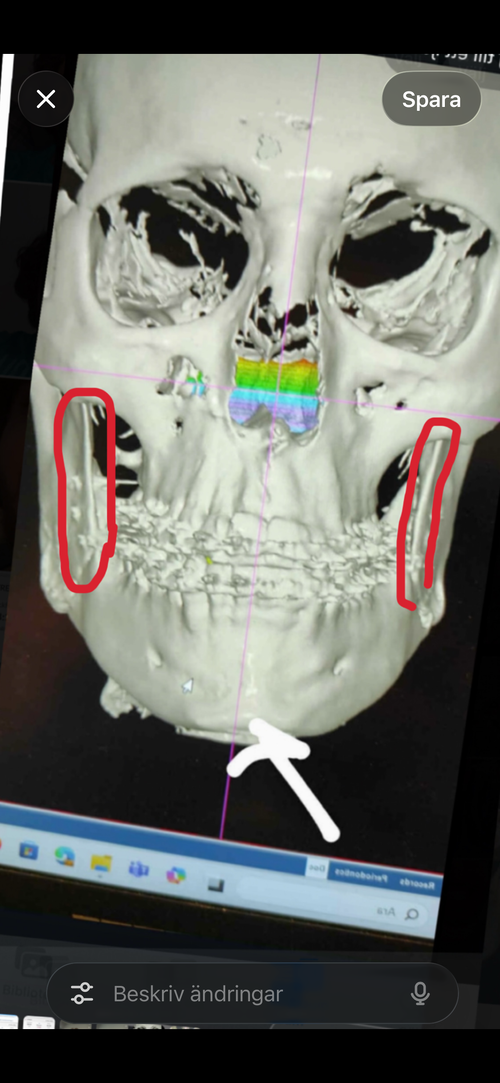

The proximal segment was torqued. Specifically, the external oblique ridge (upper ramus) was moved laterally, while the lower portion of the ramus, the gonial angle rotated inward (medially). This creates a mismatch. Increased width in the mid-ramus region, but reduced width and definition at the angles.

The circled area shows the external oblique ridge. Since the masseter attaches in this region, lateral displacement here combined with segment rotation can contribute to the inward positioning of the gonial angles and the overall distorted appearance.

Ps. Notice how my head tilt on the after cbct are totally off, that’s what happens when you do a unsymmetrical yaw rotation to correct asymmetry, how ironic. I needed to adjust the after cbct because my head leans 2-3 mm to the left now.

The proximal segment was torqued. Specifically, the external oblique ridge (upper ramus) was moved laterally, while the lower portion of the ramus, the gonial angle rotated inward (medially). This creates a mismatch. Increased width in the mid-ramus region, but reduced width and definition at the angles.

The circled area shows the external oblique ridge. Since the masseter attaches in this region, lateral displacement here combined with segment rotation can contribute to the inward positioning of the gonial angles and the overall distorted appearance.

Ps. Notice how my head tilt on the after cbct are totally off, that’s what happens when you do a unsymmetrical yaw rotation to correct asymmetry, how ironic. I needed to adjust the after cbct because my head leans 2-3 mm to the left now.